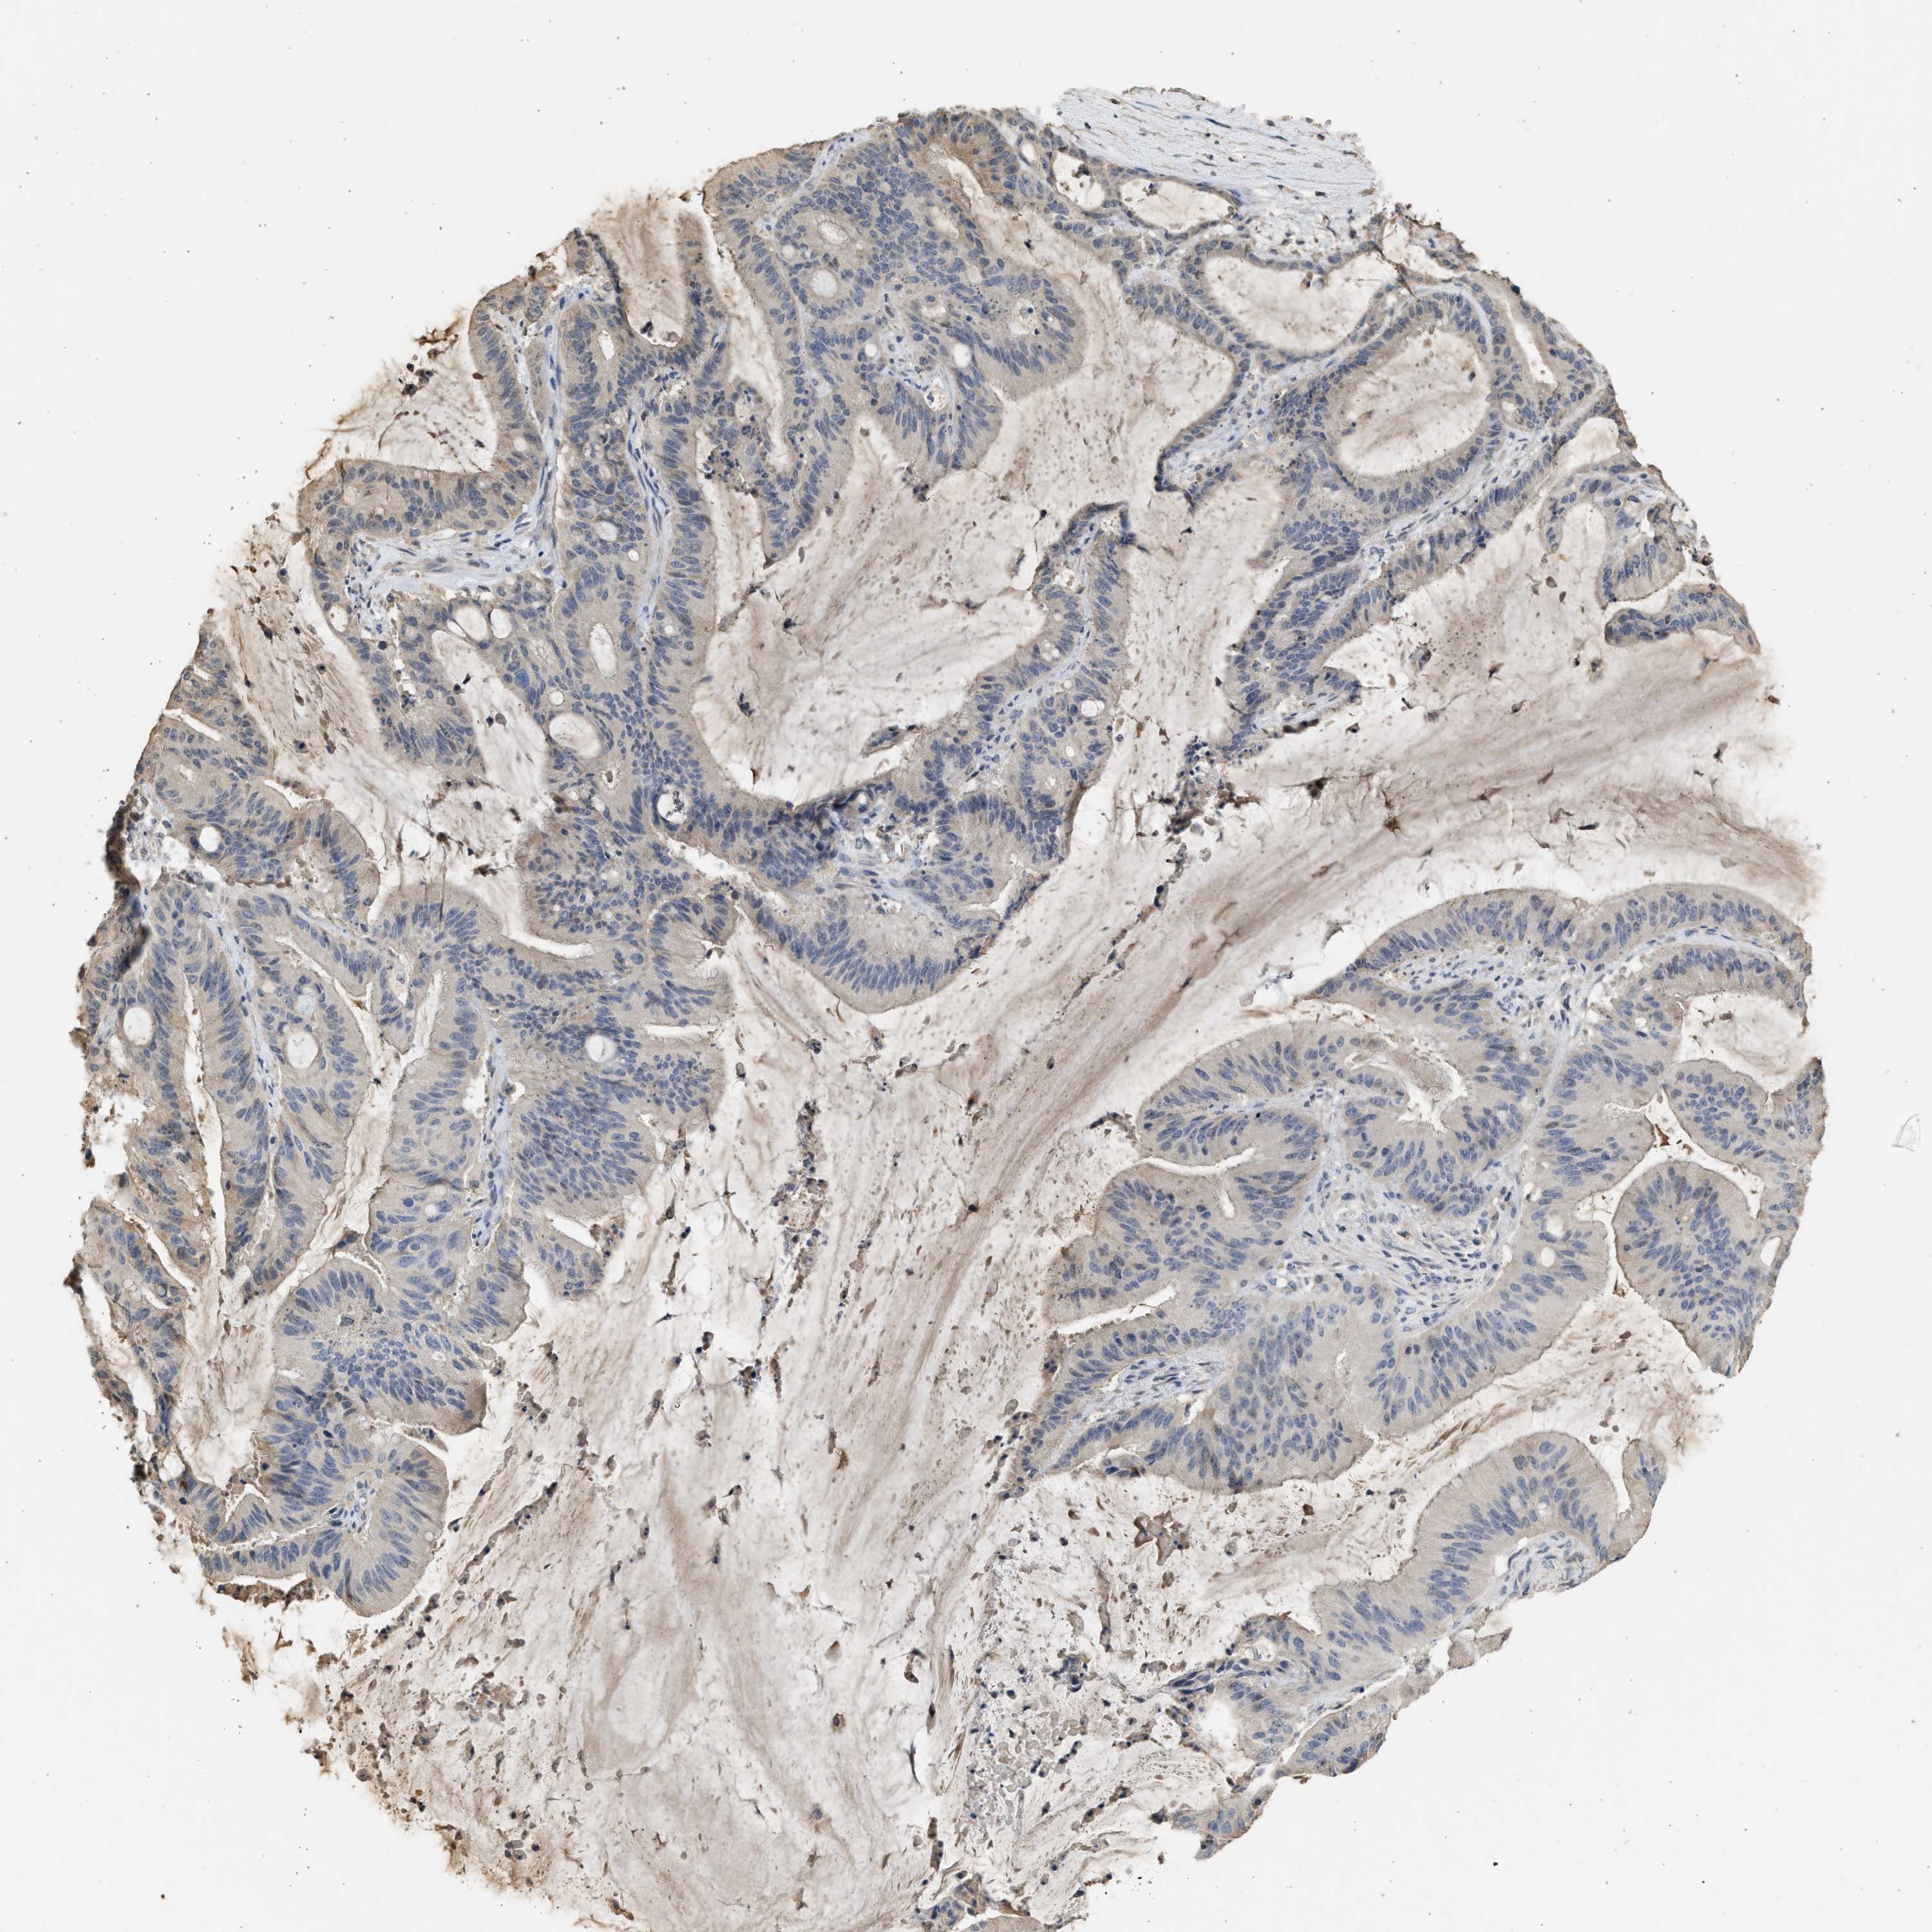

LIVER CANCER - Protein expressioni

A mouse-over function shows sample information and annotation data. Click on an image to view it in a full screen mode. Samples can be filtered based on level of antibody staining by selecting one or several of the following categories: high, medium, low and not detected. The assay and annotation is described here.

Note that samples used for immunohistochemistry by the Human Protein Atlas do not correspond to samples in the TCGA dataset.

Antibody stainingi

Antibody staining in the annotated cell types in the current human tissue is reported as not detected, low, medium, or high, based on conventional immunohistochemistry profiling in selected tissues. This score is based on the combination of the staining intensity and fraction of stained cells.

Each image is clickable and will lead to virtual microscopy that enables deeper exploration of all samples and also displays staining intensity scores, fraction scores and subcellular localization as well as patient and tissue information for each sample.

Antibody HPA041487

Antibody HPA063633

Antibody CAB018755

Staining

High

Medium

Low

Not detected

Intensity

Strong

Moderate

Weak

Negative

Quantity

>75%

75%-25%

<25%

None

Location

Nuclear

Cytoplasmic/membranous

Cytoplasmic/membranous,nuclear

Cholangiocarcinoma

Carcinoma, Hepatocellular, NOS